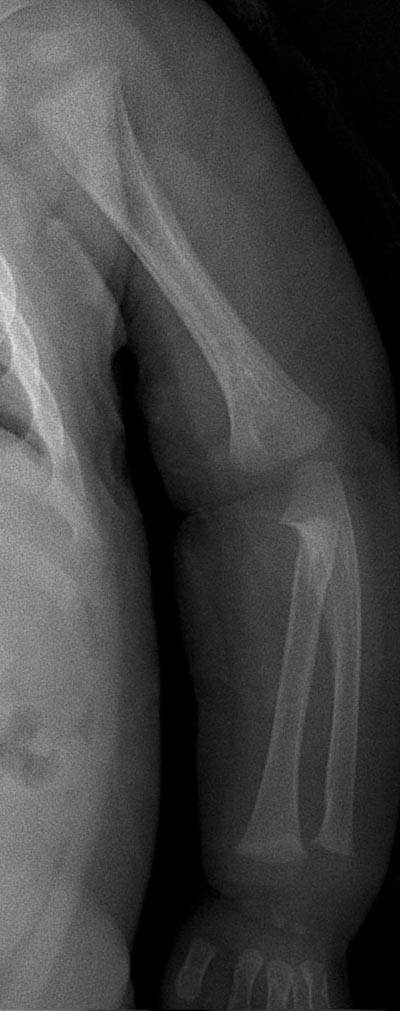

7 个月女孩,临床怀疑先天性髋脱位

干骺端宽大,杯口状变形,两侧出现骨刺,骨干增粗、骨膜增厚,考虑维生素d缺乏性佝偻病。

支持--干骺端宽大,杯口状变形,两侧出现骨刺,骨干增粗、骨膜增厚,考虑维生素d缺乏性佝偻病。建议拍肘关节正位片排除有无尺桡骨近端骨性连接。

干骺端宽大,杯口状变形,除此外还有股骨干的弯曲,另外干骺端骨质清楚,没有毛刷样表现。

请考虑一下有没有先天性疾病的可能?

本例主要表现还应是一致性连续性骨膜增厚,虽表现为干骺端宽大,杯口状变形,但无毛刷状改变,骨减少亦不明确,故个人不支持佝偻病表现,股骨弯曲我认为是正常表现,虽然后者亦可出现骨膜反应,但为次要表现且如此连续的骨膜反应还是没见过;